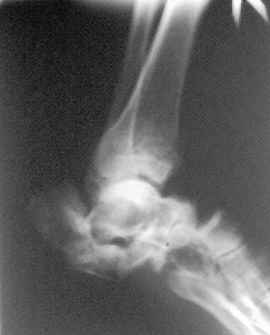

Здравствуйте,коллеги!Все оказалось даже хуже!Сегодня больной госпитализирован и:

С левой стопой дело похуже. Нужен прямой снимок, да и боковой не помешает повторить на всю стопу, ну и плюс аксиальный. Готовтье аппарат.

Отправляю снимки(свежие)и фото стоп.

С уважениемД.Б.